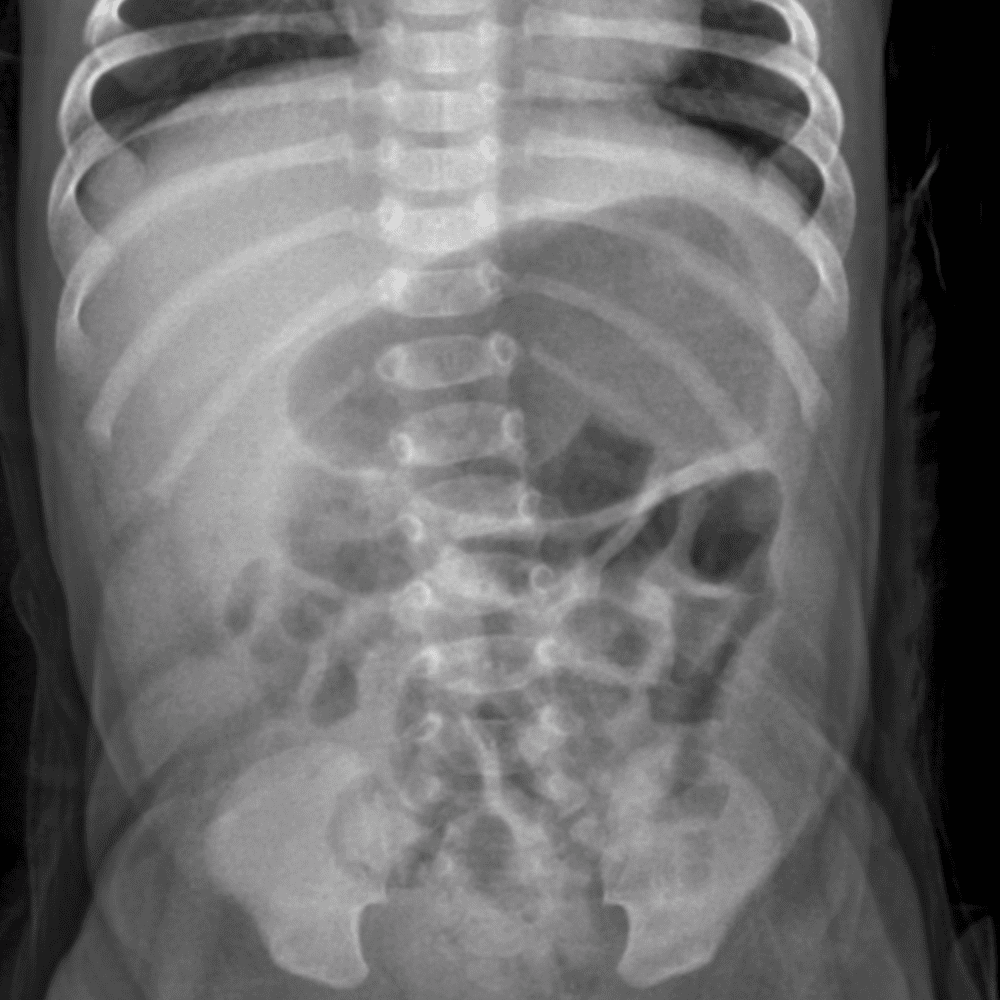

Peds Abdomen

Practice

Simulates call by including subtle or difficult cases and some normals.

30 cases